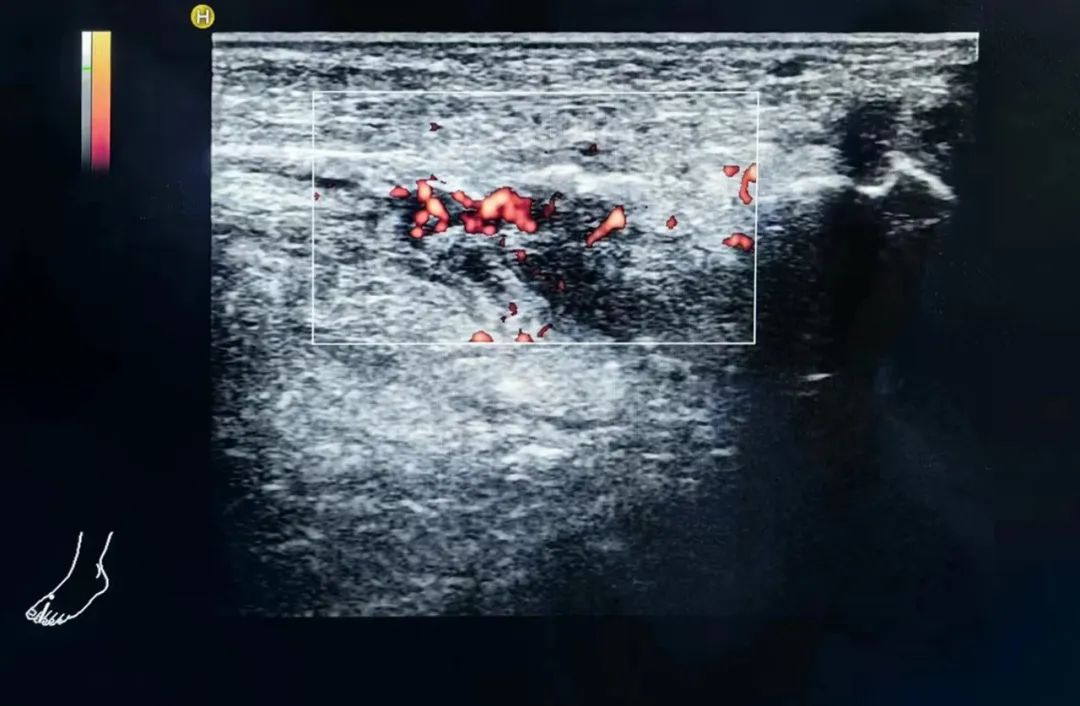

檢查過程中

醫(yī)生手持超聲探頭

在邢大叔的腳部仔細掃描

每一寸的肌膚

每一根骨頭

都仿佛被醫(yī)生的目光所穿透

終于

在左足足背的第二跖骨處

醫(yī)生發(fā)現了一個微小的骨折裂痕

周圍還伴隨著局部血腫的形成

正是這一發(fā)現

解開了邢大叔的疼痛之謎